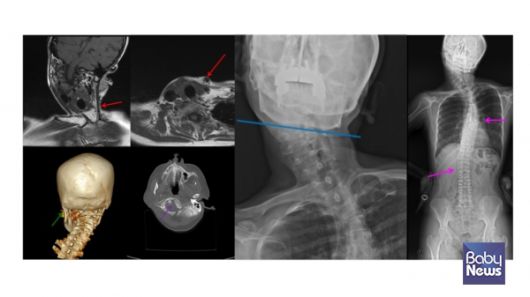

좌측 근성사경으로 인한 측경, 척추측만증 및 두개골 변형. ⓒ임신영 |

키아리 기형 1형(소뇌가 대후두공 아래로 내려오는 뇌 기형으로, 신경학적 증상을 유발할 수 있음)처럼 소뇌가 대후두공 아래로 내려오는 경우나 뇌종양 같은 중추 신경계 질환도 사경의 원인이 될 수 있습니다. 따라서 근성사경이 아니라는 이유만으로 '자세 문제’나 '습관’으로 단정하기보다는, 필요한 평가를 통해 기저 질환이 없는지를 확인하는 과정이 중요합니다.